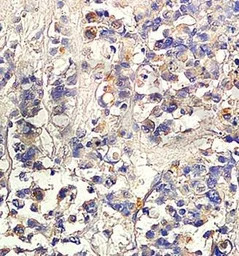

IHC-P analysis of human colon carcinoma tissue using GTX37528 TGF beta 2 antibody.

IHC-P analysis of human colon carcinoma using TGF beta 2 antibody.